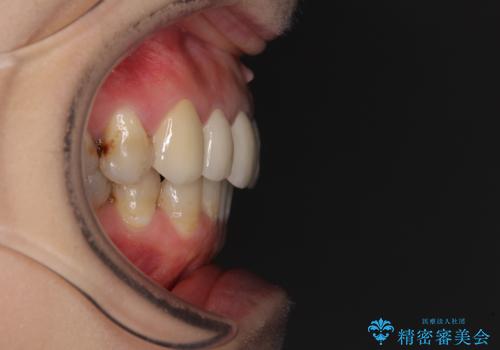

- 前歯の歯並びやむし歯治療の跡、奥歯の銀歯を気にして来院された患者様です。

インビザラインによる矯正治療の後に虫歯や銀歯をセラミックにて補綴することとしました。

前歯のむし歯治療の跡や奥歯の目立つ銀歯がなくなり、明るい口元になりました。